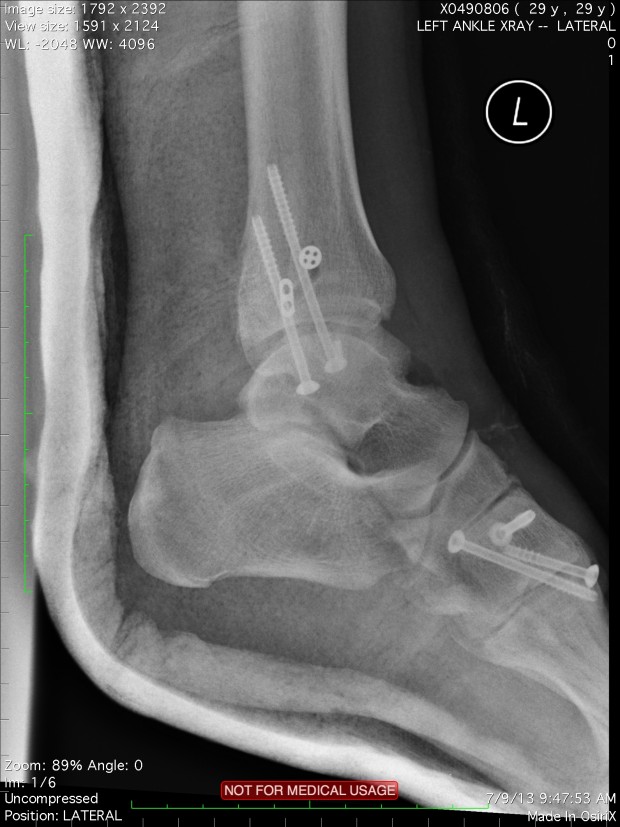

Robby Swift is recovering from his injury right here in the UK, from the looks of this picture, he’s got a fair few screws keeping it all together! As ever, fingers crossed and we all with Swift a speedy recovery.